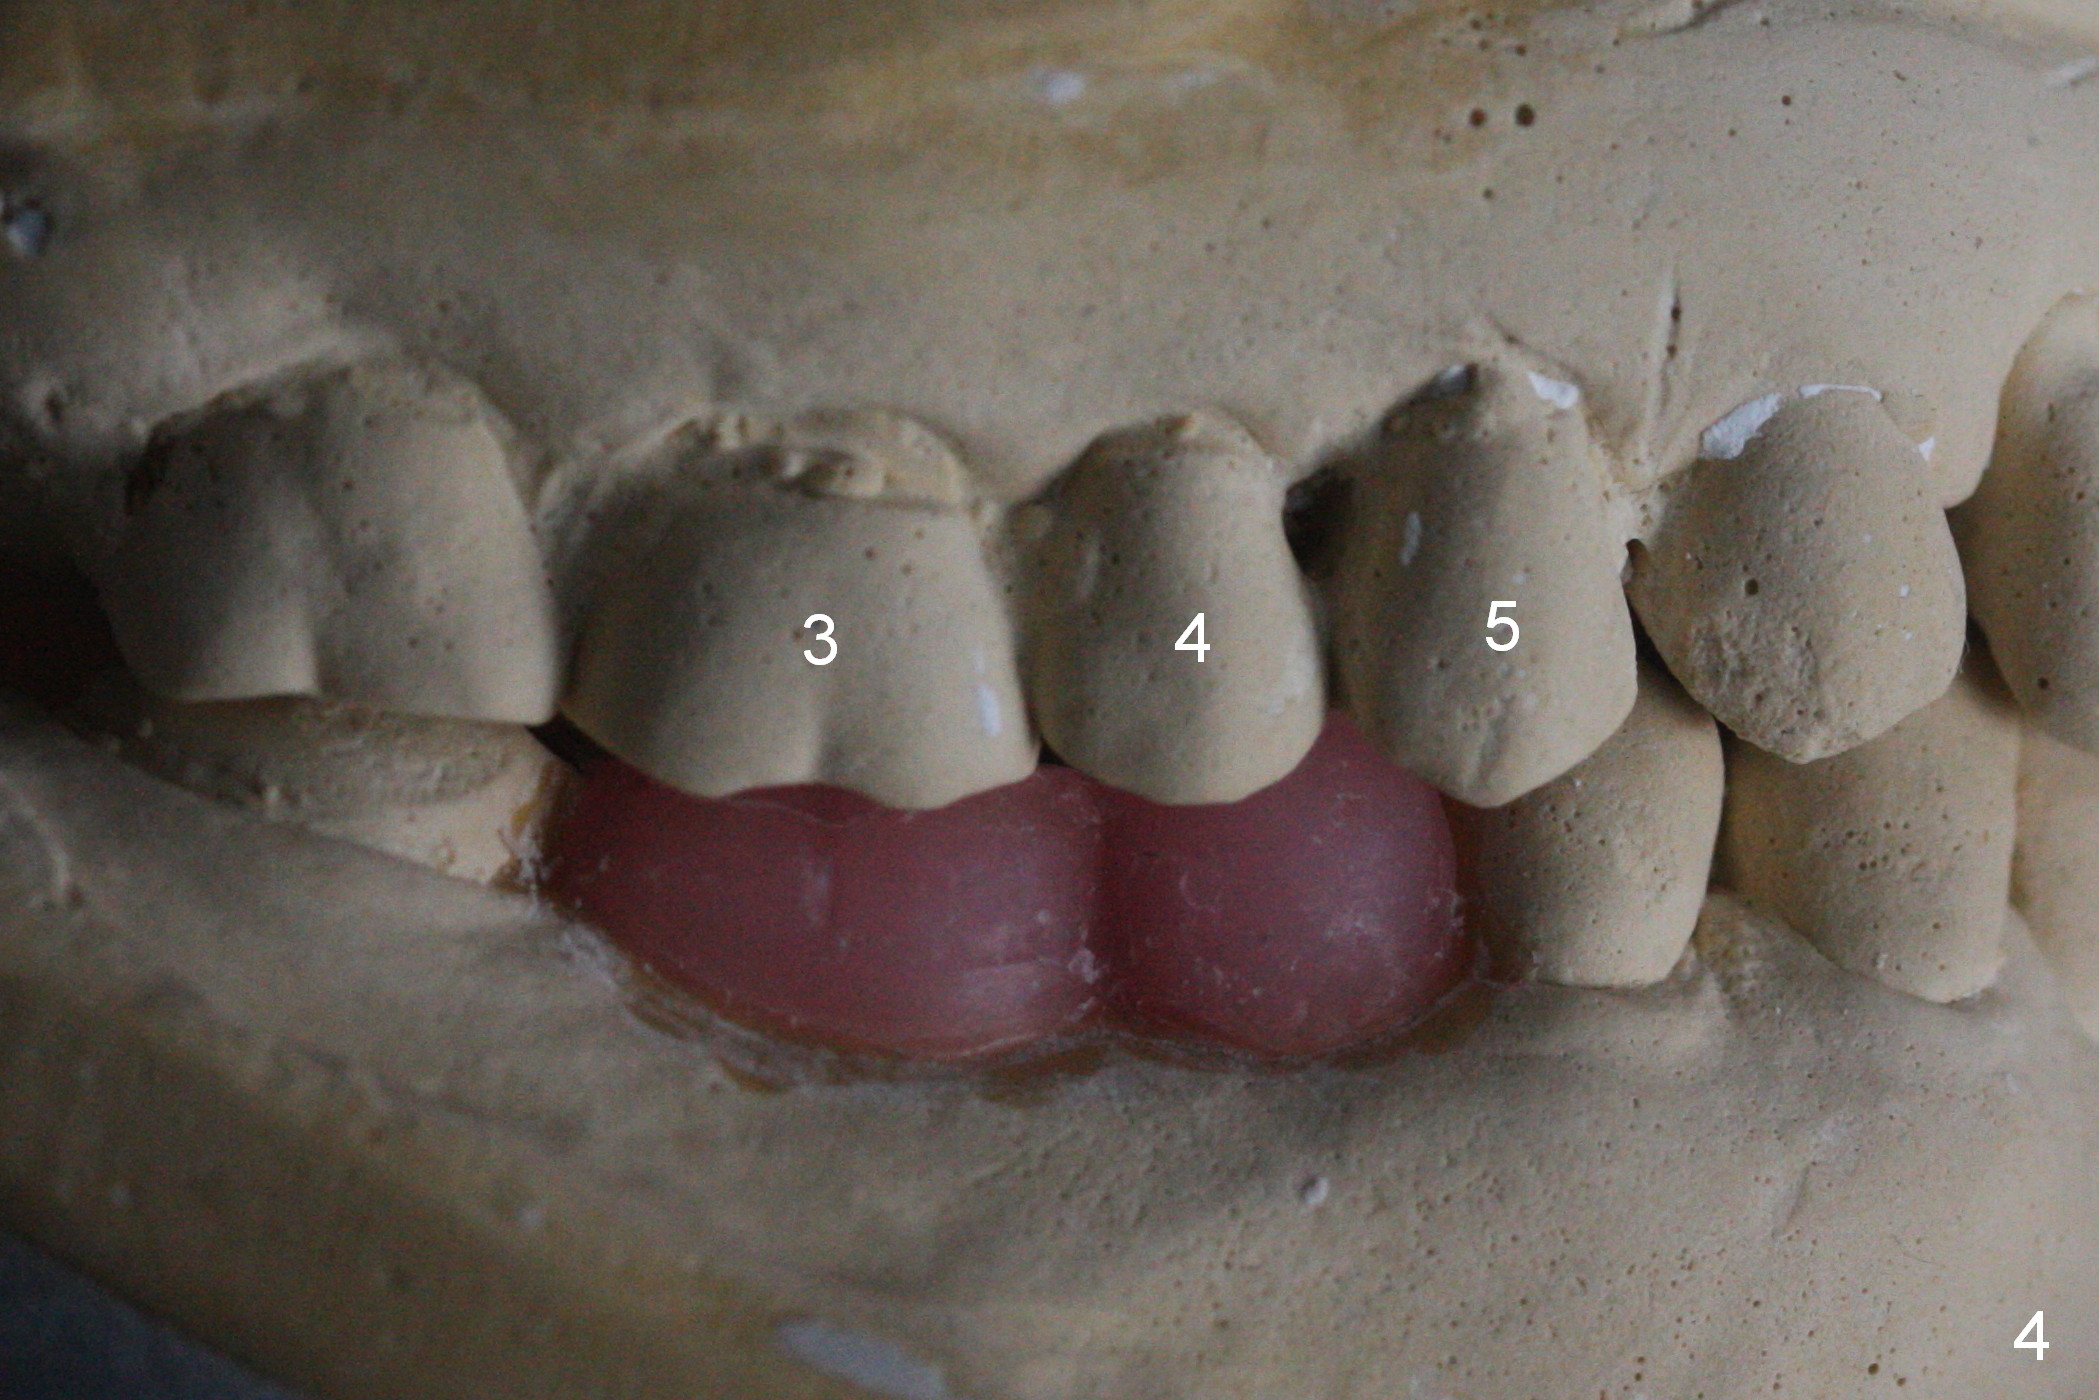

The ridge appears to be not so narrow (Fig.3). The opposing teeth (#3-5) are slightly supraerupted (Fig.4).